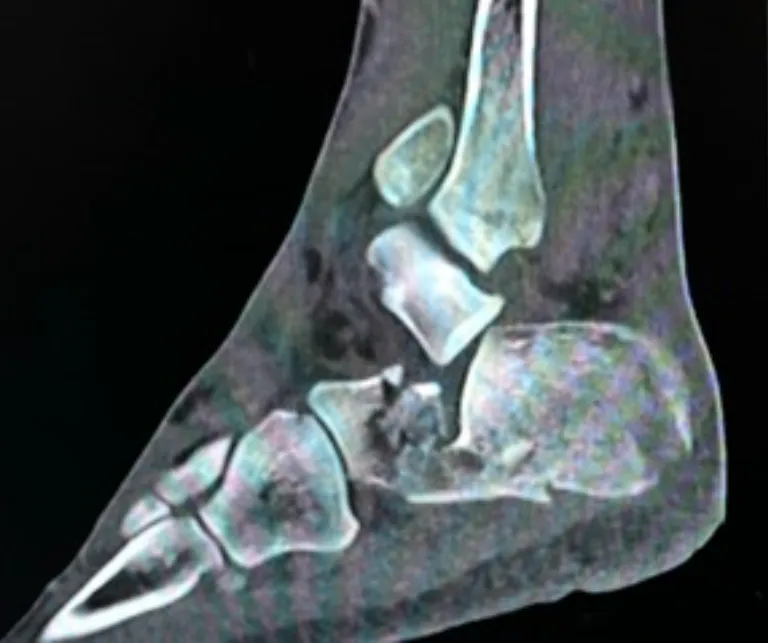

A CT scan is essential to accurately evaluate:

- The degree of articular involvement

- The number of fracture fragments

- Joint displacement

- Overall fracture morphology

The CT will identify the severity of the injury and whether surgery is indicated or not.

Severity is determined on the CT by:

- The degree of joint displacement

- Sanders classification on CT